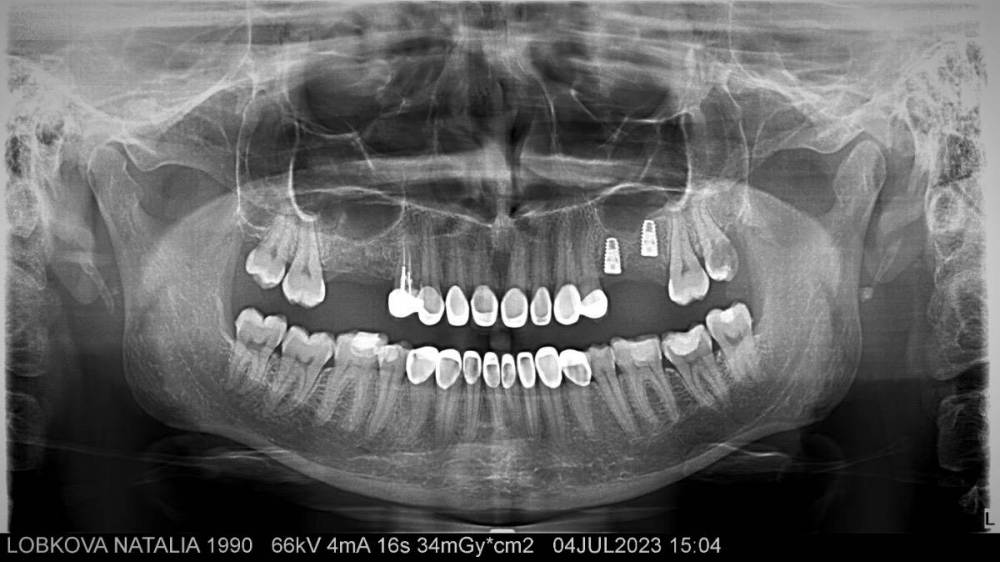

Наталья1306 Опубликовано 6 июля, 2023 Поделиться Опубликовано 6 июля, 2023 Здравствуйте. Четыре месяца назад поставила два импланта с наращиванием костной ткани. С тех пор у меня до конца не спадает отек. Очно была на консультации у трех стоматологов, специализирующихся на установке имплантов, вердикт первого: есть свищ, импланты плохо закрепились, лучше их удалить. Вердикт второго: нет свища, есть киста, ее нужно удалить, с имплантами все в порядке. Вердикт третьего: нет ни свища, ни кисты, ни воспаления вокруг имплантов, а мои дискомфортные ощущения вызваны натяжением мягких тканей, что является нормой после имплантации. Кому верить, естественно, не понятно. Ссылка на 3D снимок ( открывается только на компьютере) https://drive.google.com/file/d/1EBbGWJhpeiqCE-XebMQu9apqPMveobT1/view?usp=drive_webhttps://drive.google.com/file/d/1EBbGWJhpeiqCE-XebMQu9apqPMveobT1/view?usp=drive_web Ссылка на комментарий

Bier Опубликовано 6 июля, 2023 Поделиться Опубликовано 6 июля, 2023 не вижу кисты и какого-то воспаления на этом снимке, свищ надо искать глазами во рту или по фото хотя бы Ссылка на комментарий